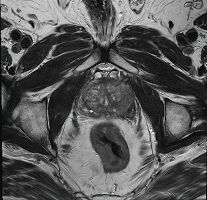

PROSTATA-

MRT

Mit mehr als 60.000 Neuerkrankungen pro Jahr in Deutschland ist das Prostatakarzinom (Krebs der Vorsteherdrüse) die häufigste Krebserkrankung bei Männern.

Bei einer frühzeitigen Erkennung bestehen bei dieser Tumorart sehr gute Heilungschancen.

Es stehen unterschiedliche  Früherkennungsmethoden wie z.B. Sonographie und Bestimmung des PSA-Wertes zur Verfügung.

Ein zusätzliches aussagekräftiges Untersuchungsverfahren stellt die multiparametrische MRT (Magnetresonanztomographie)  des Prostataorgans dar.

Wir bieten diese Methode an unseren Standorten Calw und Leonberg routinemäßig an.